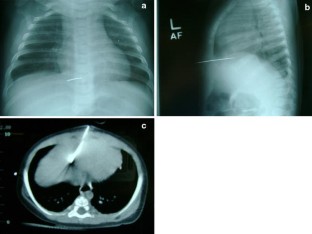

Fig. 1

Fig. 2

Fig. 3